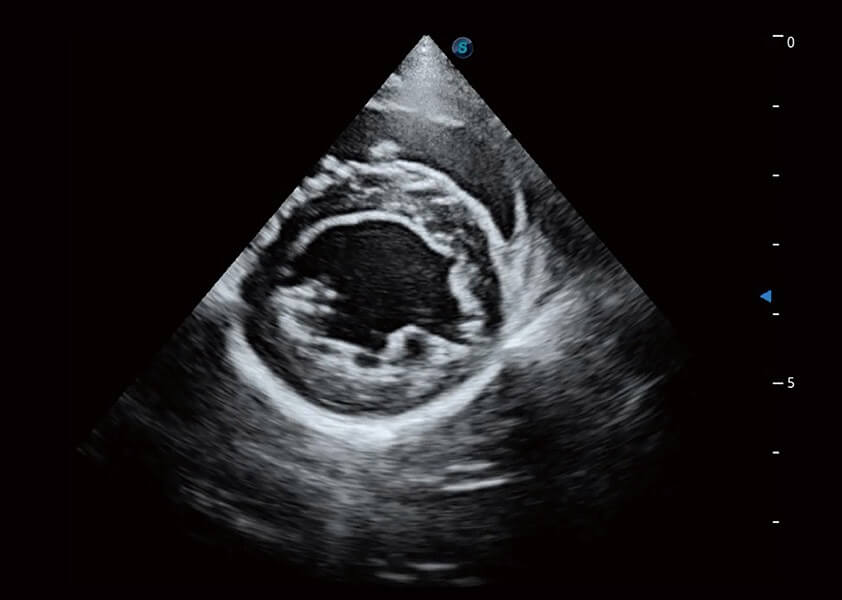

ProPet 60 作为一款高端台式动物超声设备,为动物医生的日常诊断提供了一系列贴合动物临床需求、解决临床实际问题的高级成像功能。凭借全系列高清探头,满足医生对腹部、心脏、生殖、浅表、肌骨等成像的所有需求,切实帮助您提升检查效率,提高诊断信心。

兽用彩色多普勒超声诊断系统

动物是人类最亲密的朋友和最值得信赖的伙伴。百老汇电子游戏官网也一直致力于探索动物专用的超声影像解决方案。 全新推出的ProPet系列,是百老汇电子游戏官网在动物超声影像智能化、专业化、精准化的一次跨越式革新。动物不能用言语来表述自己的不适,通过超声影像,ProPet系列搭建了动物医生与不同物种沟通的“桥梁”,为动物医生注入了“治愈之力”。